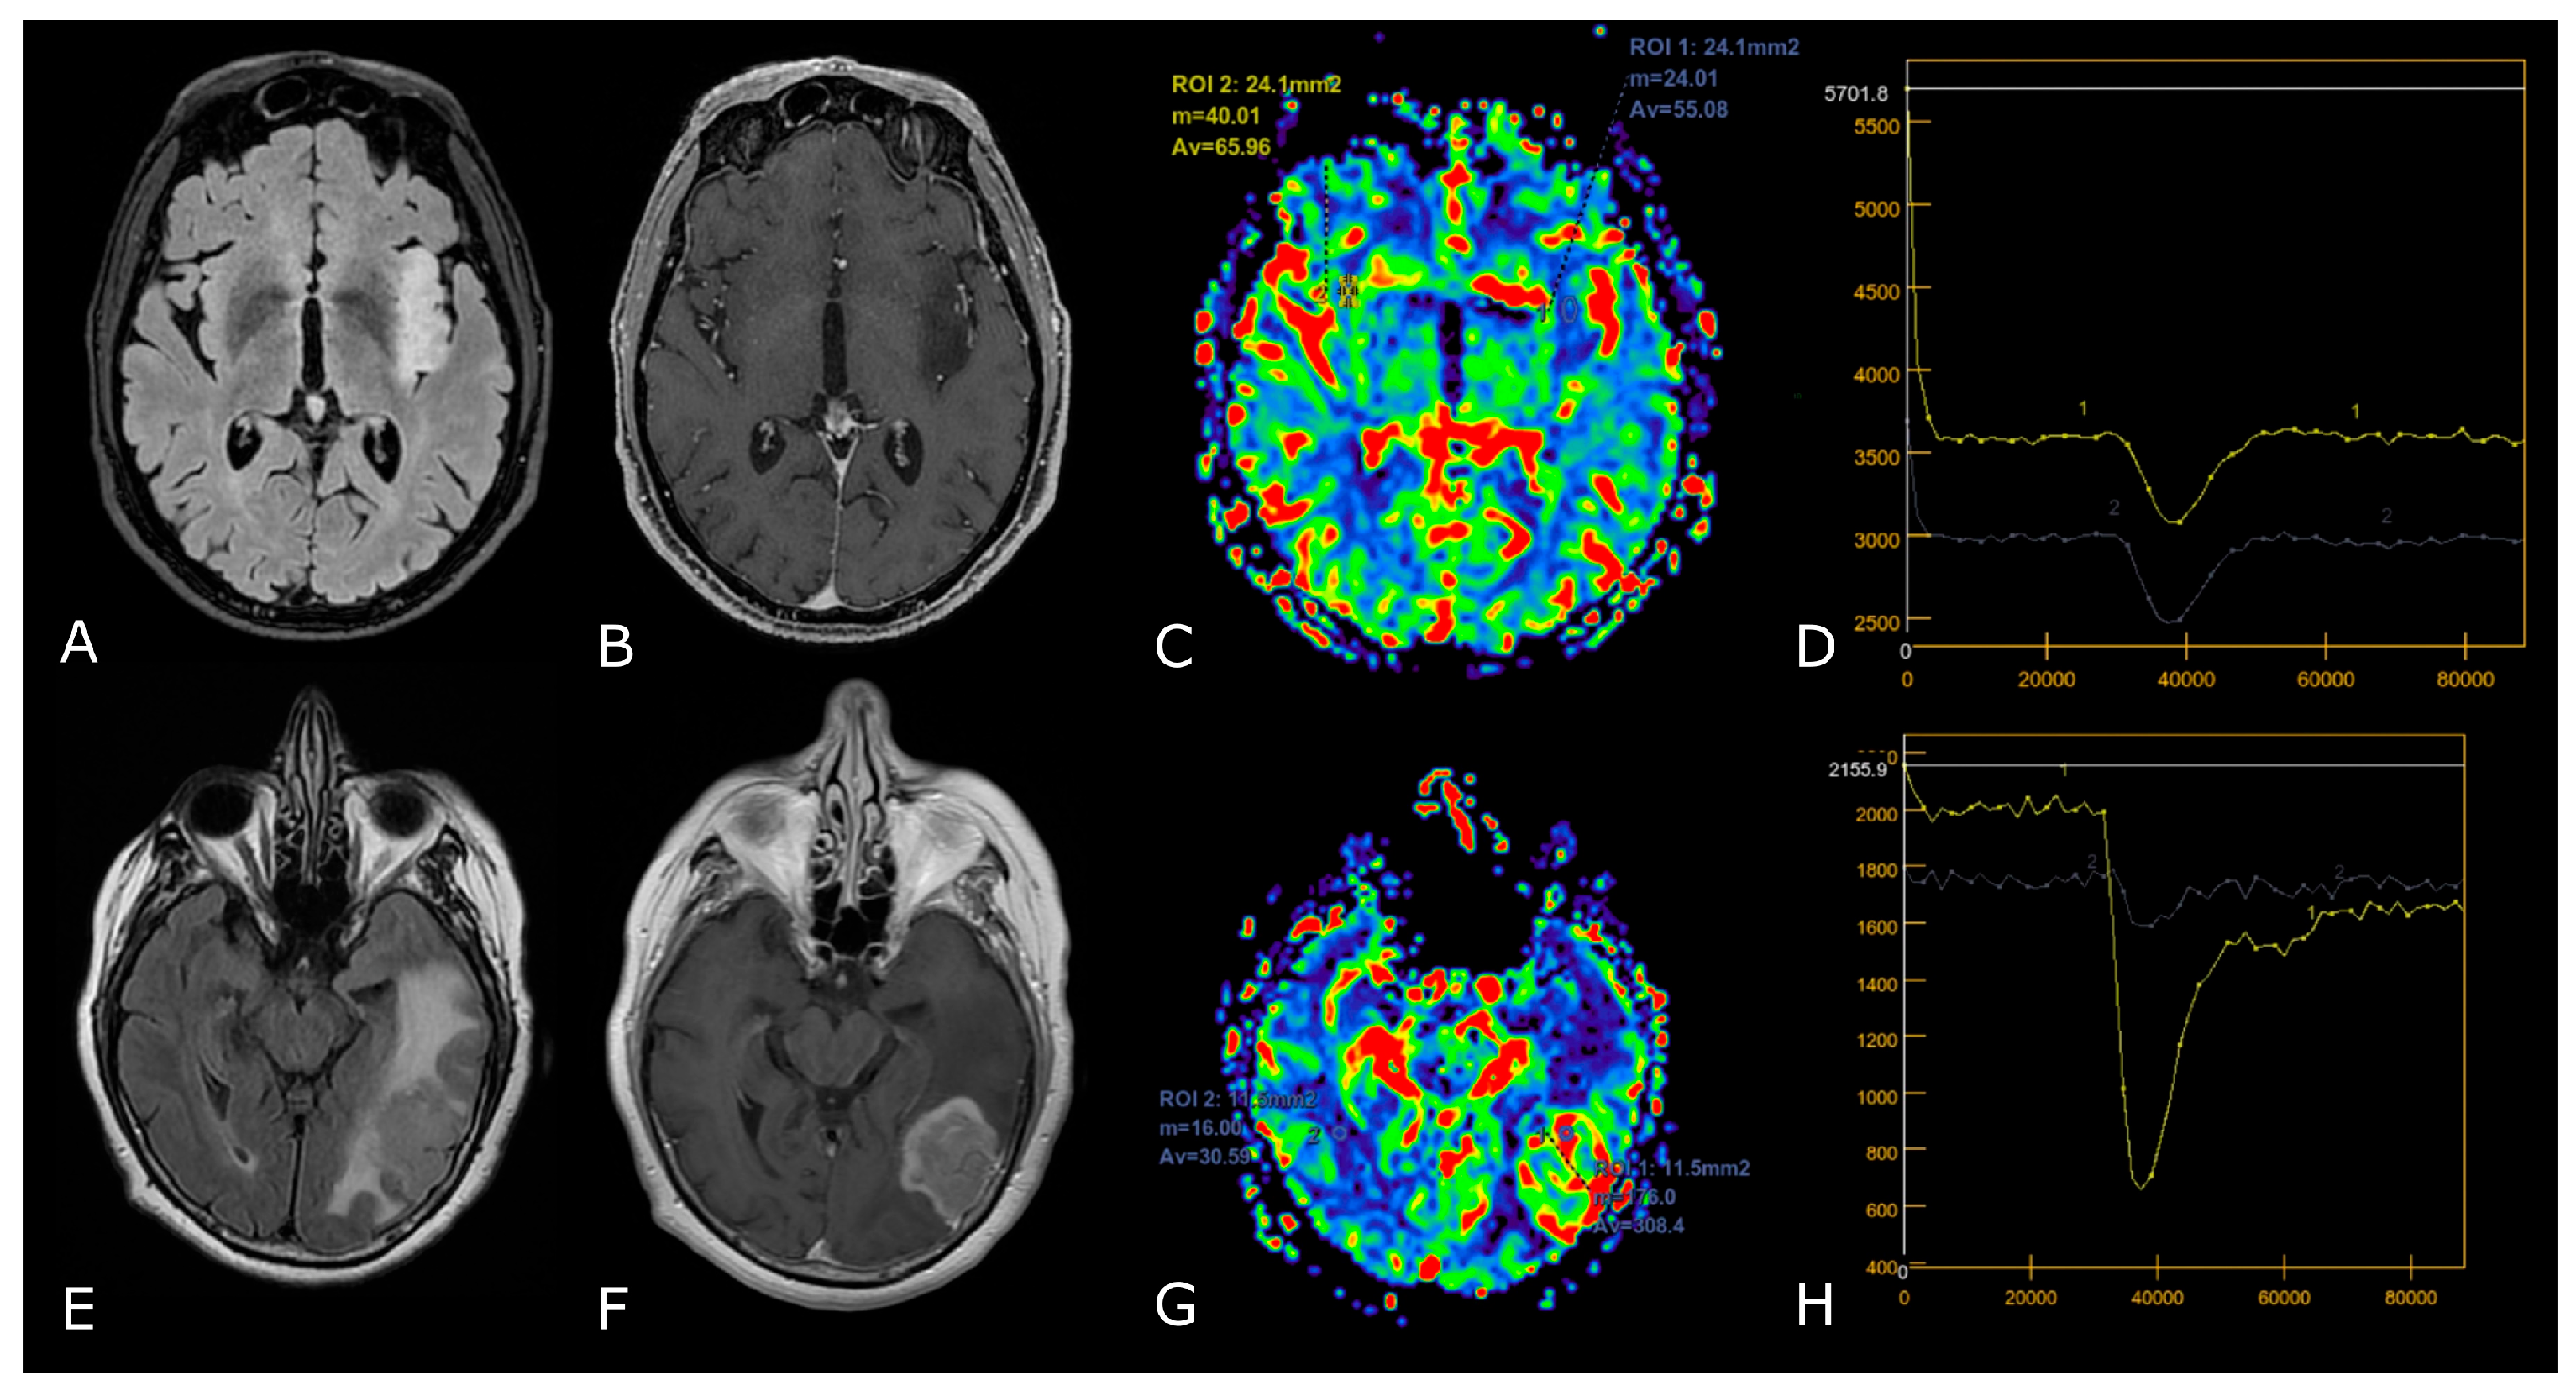

Figure 4.

DSC-PWI in differentiating HGG from LGG. Axial T2-FLAIR (A) and post-contrast T1w (B) of a low grade IDH-mut left insular astrocytoma. DSC-PWI demonstrates normal rCBV (C) and complete return to baseline of the signal-intensity-time curve (D). The second row shows axial T2-FLAIR (E) and post-contrast T1w (F) of a left temporal-occipital GB. DSC-PWI demonstrates increased rCBV (G) and reduction of PSR consistent with BBB breakdown (H).

The differences between PsP and radiation necrosis (RN) are related both to the timing of presentation, i.e., 3–6 months for PsP and 1 year after RT in RN, but also to the different pathophysiology whereby RN presents as permanent damage to the brain tissue, necrosis, and vascular thrombosis [35,36,37]. Many DSC studies have shown that CBV is lower in areas of RN or PsP than in those of tumor progression. DCE studies are less numerous but have shown that patients with PsP and RN had significantly lower Ktrans values than patients with tumor progression (Figure 5) [23,29,30,31,35,36,37]. Studies focusing on PsP or RN specifically using ASL are scarce, but one study confirmed that the normalized ASL-CBF ratio was significantly higher in tumor progression than in radiation injury [38].

Figure 5.

Post-treatment changes vs. disease progression. (A–H): axial 3D-FSPGR post-contrast T1w images (A,E) and T2w images (B,F) with corresponding DSC-CBV (C,D) and DCE-Ktrans perfusion maps (G,H) of two IDHwt GBs 1 year after treatment (surgery and radio-chemotherapy). In the left panel the enhancing tissue shows low DSC-CBV and DCE-Ktrans, consistent with post-treatment changes. In right panel the enhancing tissue shows areas of increased DSC-CBV and DCE-Ktrans, suggesting disease progression.